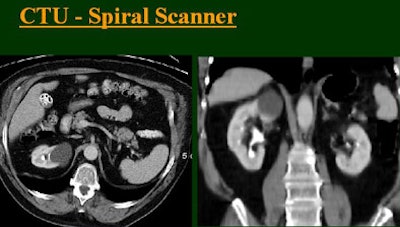

At the 2004 RSNA meeting in Chicago, Dr. Vassilios Raptopoulos from Massachusetts General Hospital and Harvard Medical School in Boston evaluated single-, four-, eight-, and 16-row detector scanners in 200 patients using a single-acquisition biphasic CT urography (CTU) protocol. As the number of detector rows increased, visualization -- especially of the calyces -- improved significantly.

Raptopoulos said that for most patients a single biphasic split-bolus CT urography scan -- combining the corticomedullary and excretory phases -- provides most of the information available in a higher-dose two-series acquisition. Except in a few situations requiring a very detailed look at contrast dynamics in two separate acquisitions, the single-scan approach is robust enough for CTU and general abdominal CT as well. And the split-bolus technique seems to produce better results every time the group gets a new scanner, he said.

"As we've been scanning through the kidneys, we've been noticing that there has been an increase in the quality images as we go from (single-) to four-, eight-, and 16-row detector scans," Raptopoulos said. "Our purpose, then, was to assess the quality of CTU with progressively improving CT technology from (single-) to 4-, 8-, and 16-row scanners, using a split-injection single scanning technique."

| Top to bottom: Split-bolus CTU improves significantly using a nearly identical protocol but with the addition of more detector rows, from single- (spiral), four-, eight-, and 16-row scanners. All images courtesy of Dr. Vassilios Raptopoulos. |

The group examined 200 patients referred for CTU over an eight-month period, and divided them into four groups of 50 each that underwent either single-, four-, eight-, or 16-row CTU (The first three scanners were from GE Healthcare, Chalfont St. Giles, U.K.; the 16-row machine was from Toshiba America Medical Systems, Tustin, CA.)

The patients were prepped with about 4 cups of water 30-60 minutes before the study. A noncontrast series was obtained first, followed by contrast-enhanced scanning using the split-bolus technique. The patients received 50 mL of nonionic IV contrast at 2.5 mL/sec without being scanned, then two minutes later an additional 100 cc of contrast was administered at 2.5 mL/sec, and images were acquired from the diaphragm to the symphysis 60 seconds after the second injection.

The single-row scanner required two breath-holds; the other scanners reduced scan time from about 20 seconds (four-slice) down to seven seconds (16-slice). Collimation for the single-row scanner was 5 mm, with 3-mm overlapping reconstructions. Collimation for the four-, eight-, and 16-row scanners was 2.5 mm, 1.5 mm, and 0.5 mm, respectively, with the patients scanned in a prone position.

Visualization of the calyces was evaluated subjectively on a scale of 1 to 5, with 1 representing no visible architecture and 5 representing sharply cupped calyces. The filling of the upper and lower ureters was also scored: 1 for no filling, 3 for half filled, and 5 for completely filled.

Based on multiplanar reformatted (MPR) images, there was significant upscale improvement in calyceal detail from the isotropic images provided by single-detector scanning (median score 2) to four- (median score 3), eight- (median score 4), and 16-detector scanning, Raptopoulos said. On MPR images the calyceal were 1, 2, 3, and 5, respectively. The median ureteral filling was 4 for the upper and left-lower ureters, and 3 for the right-lower ureters.